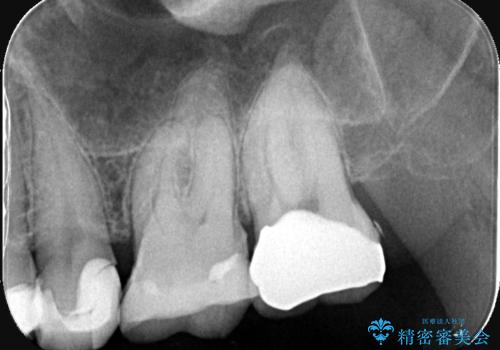

- 患者様は、左上7のメタルインレー(銀の詰め物)の見た目が気になるとのことで来院されました。診察したところ、メタルインレーの下にむし歯の再発リスクがあることも確認。より審美性と耐久性を高めるため、メタルインレーを除去し、セラミッククラウンで補綴する治療計画を立てました。

メタルインレーを丁寧に除去し、歯の状態を確認。その後、精密な形成を行い、適合性の高いセラミッククラウンを装着しました。セラミッククラウンは天然歯に近い見た目で、美しさだけでなく強度や機能性にも優れているため、患者様にも「自然な仕上がりで違和感なく噛める」と大変ご満足いただきました。